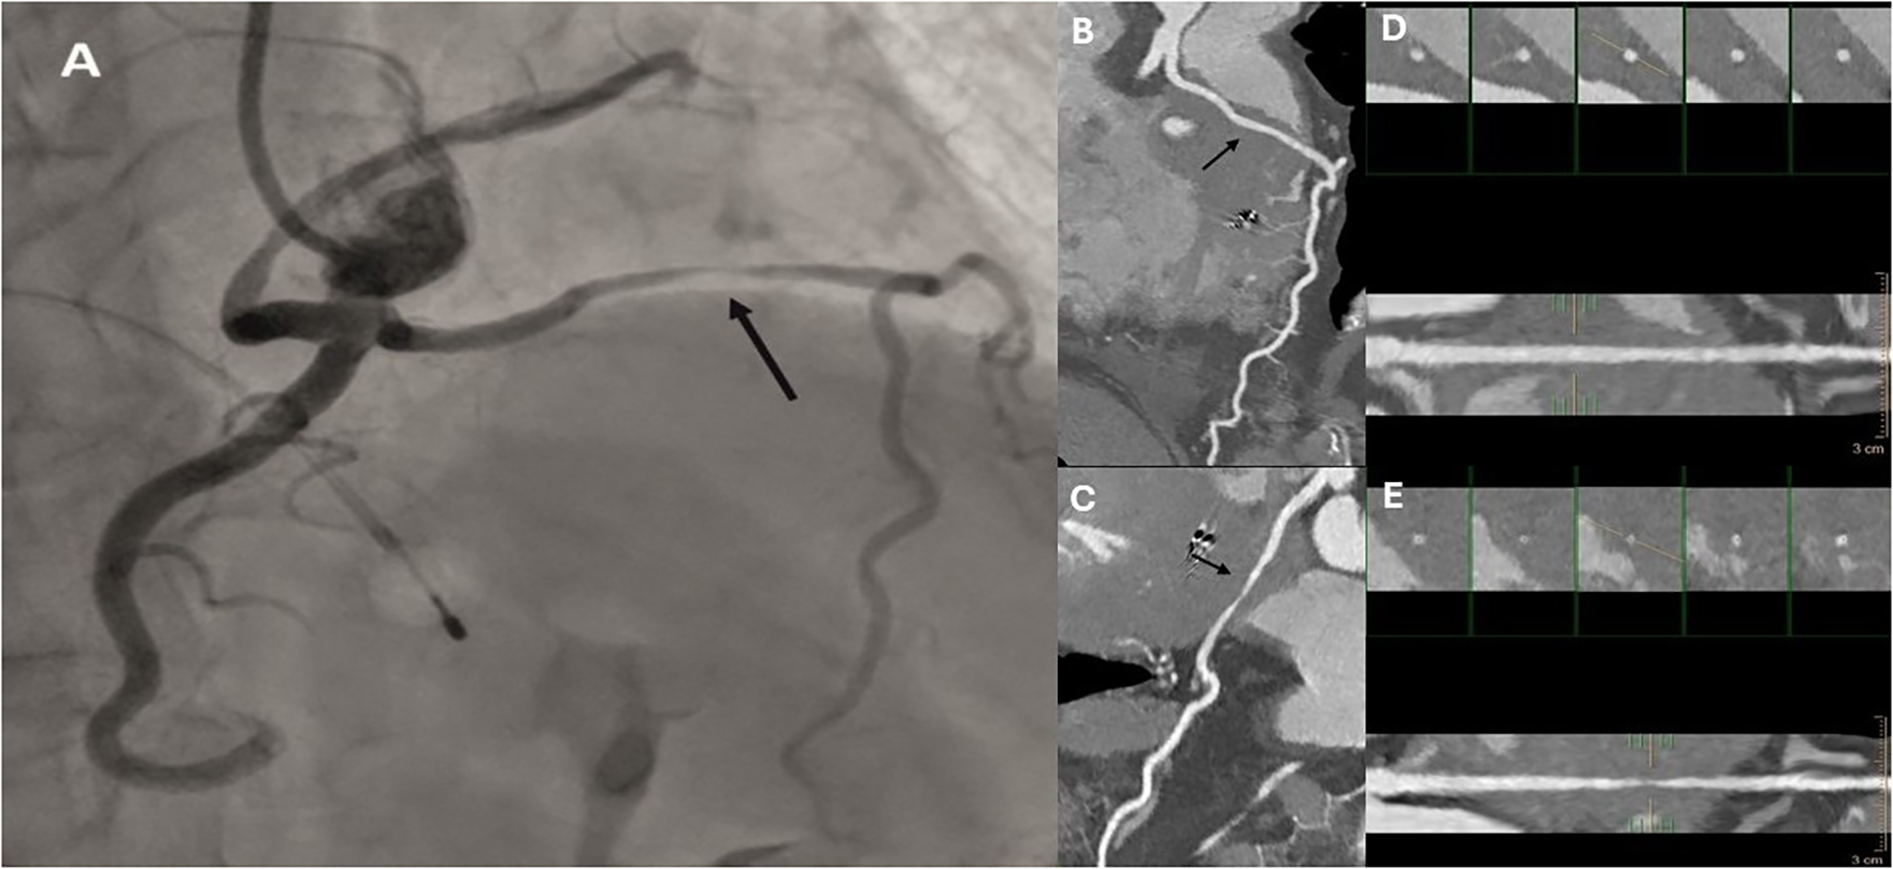

Figure 2

Invasive coronary angiography (A) and multiplanar reconstruction cardiac CT (B) with microcoil in septal branch acute take-off (red arrow) and microcoil (black arrow) positioned in the largest septal branch—figure 2A; micro coil in septal branch (black arrow)—figure 2B.

On the second attempt, same guiding catheter and coronary guidewires were used. The embolization of septal branch was successfully done with two 2mm × 2 cm Azur Cx micro coil (Terumo Europe, Leuven, Belgium). (Figures 2A,B) During the procedure, echocardiography confirmed akinesia of the basal and mid septum, with a reduction in the LVOT velocities from 7.24 to 1.5 m/s, leading to a corresponding reduction in LVOT gradient from 209 mmHg to 9 mmHg. The procedure was completed successfully (Figures 1A–C), and the patient was discharged after 3 days with telemetry monitoring.

At six months post-procedure, CTCA demonstrated occlusion of the septal branch, with prominent metallic artifact at the site of coil deployment and absence of post-contrast opacification both proximal and distal to the coil, consistent with a lack of residual flow through the septal branch (Figure 2B). Additionally, CTCA identified a rare congenital coronary anomaly consistent with an SCA, which was classified as type R-III. In this variant, the LAD and LCx arteries originate separately from the proximal segment of the normally positioned right coronary artery (RCA), with absence of a left main coronary artery (LCA) (Figure 3, Supplementary Video S1–S2). A segment of the LAD courses through the interventricular septum, forming a myocardial bridge, which is considered a potentially “malignant” S subtype (Figures 4A–E).

Figure 4

Invasive coronary angiography (A), curved multiplanar reconstructions (B,C), and cross-sectional vessel analysis (D,E) demonstrating a myocardial bridge (black arrows). Images are shown in both diastolic (B,D) and systolic (C,E) phases of the cardiac cycle, highlighting dynamic compression of the bridged coronary segment.